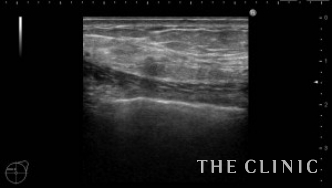

左)吸引後、しこりは消失しました。右)吸引した壊死している脂肪です。